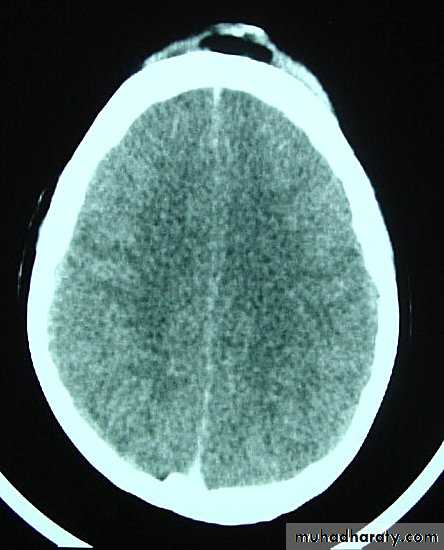

1. Diffuse Axonal Injury

Prolonged post-traumatic state in which there is loss of consciousness from the time of injury that continues beyond 6 hours.

Occurs as a result of mechanical shearing at the grey-white matter interface.

This causes disruption and tearing of axons, myelin sheaths and blood capillaries.

Severity can range from mild damage with confusion to coma and even death.